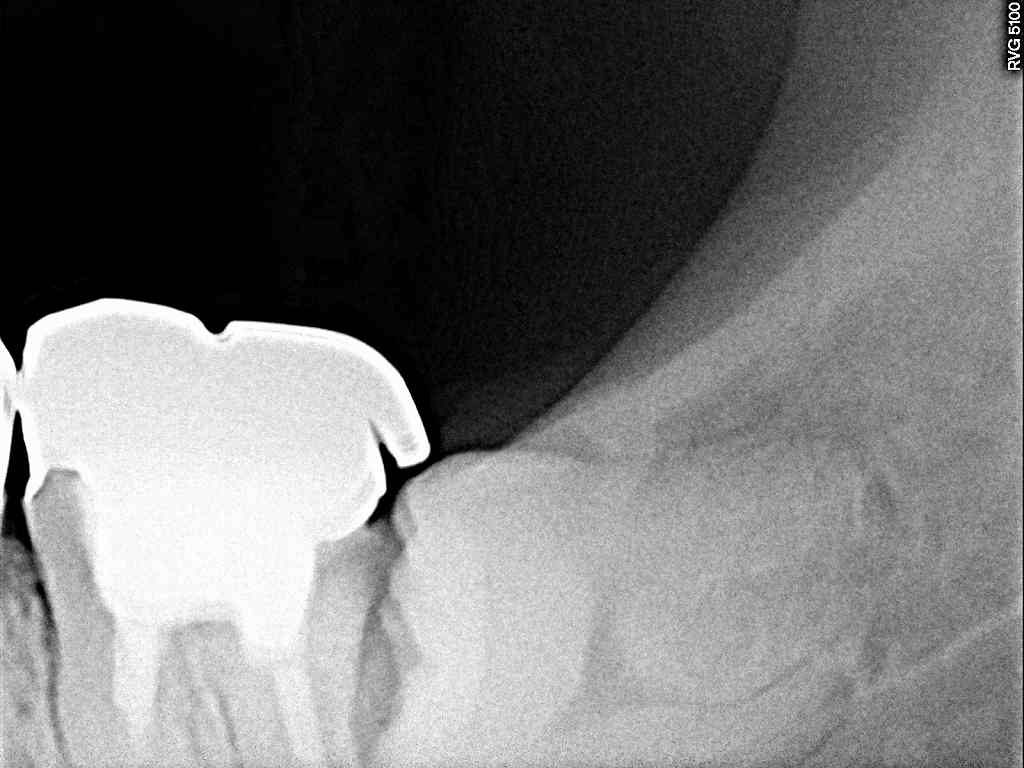

この銀歯の歯は7番になります

デンタルレントゲンでも親知らずが悪さをして

7番の遠心部に虫歯を作っていました